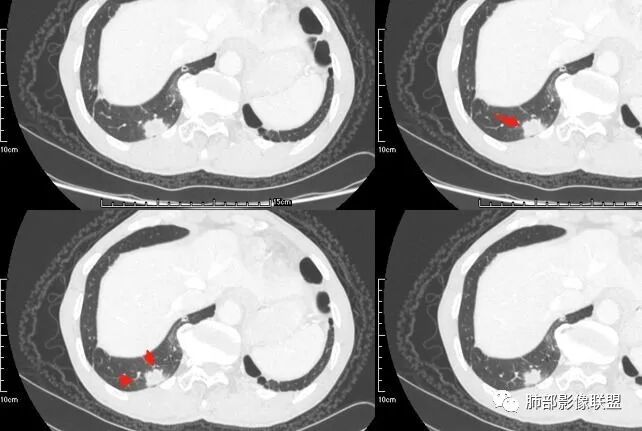

本病例左肺下叶肿块,有深分叶、毛刺、胸膜牵拉凹陷、支气管截断及纵隔内淋巴结肿大等征象,都均支持病灶为恶性,如腺癌,而且叶间裂的多发结节也提示是腺癌来源可能大;双肺多发结节、肿块,大部分病灶有分叶、毛刺及胸膜凹陷的恶性征象,与原发肿瘤本身的性质有关,所以应该与左肺下叶肿块同源,而且双肺多发病灶内空洞也具有多样性;

此病例中空洞形态多样,内壁不光整,有分隔影,周围未见明显卫星灶及钙化灶,结核不太符合;患者病史慢性病史,无明显发热,缺乏中毒临床表现,急性感染基本排除;各种中性粒细胞胞浆抗体阴性,没有鼻窦炎,肾脏等病史,基本排除血管炎;霉菌性空洞常见于免疫机能低下者, 常为空洞、肺炎、伴“ 晕圈”征的结节及支气管扩张合并存在。